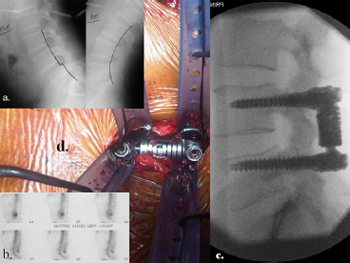

5.4.1. Illustrative patient 4

A 47-year-old woman positive for hepatitis C and human immunodeficiency

virus presented with L1/L2 osteomyelitis. The patient

had developed progressive pain and leg weakness over 2 months

with vertebral body collapse and gross mechanical instability at

L1/L2. Open surgery was not offered due to her pre-morbid status

and high-risk to the surgical team. Percutaneous stabilisation of

the progressive kyphosis/vertebral body collapse was offered. Surgical

time was 1 hour, 55 minutes with 120 mL of blood loss. The patient

was mobilised on day 1 with significantly reduced pain scores

and discharged to the infectious diseases team. Follow-up at 4

months revealed bone union across the L1/L2 interspace.

Fig. 13. Illustrative patient 4, a 47-year-old female, positive for hepatitis C and

human immunodeficiency virus, with L1/L2 osteomyelitis. (a) Sagittal T2-weighted

MRI showing L1/L2 osteomyelitis; (b) sagittal CT scan reconstruction showing

progressive kyphosis; (c) intra-operative photograph showing percutaneous pedicle

screw fixation; and (d) post-operative lateral image intensifier radiograph showing

a reduction of deformity and restoration of sagittal alignment.